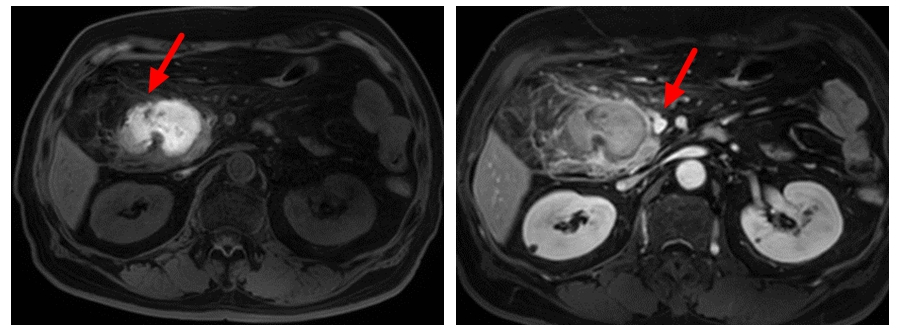

到医院就诊时 , 黄阿婆的腹胀症状已比较严重 。 超声检查发现 , 盆腔内附件区有14.3cm*8.6cm*11.3cm大小的囊性回声;入院后全腹CT提示 , 盆腔右中下腹部有巨大囊性肿块 。

“育龄女性正常卵巢大小是4cm*3cm*1cm , 绝经后妇女的卵巢会逐年萎缩 。 ”姚婷婷介绍 , 黄阿婆绝经几十年了 , 附件区却有个十几厘米的包块 , 需要格外注意 , 随时都有破裂的可能 。